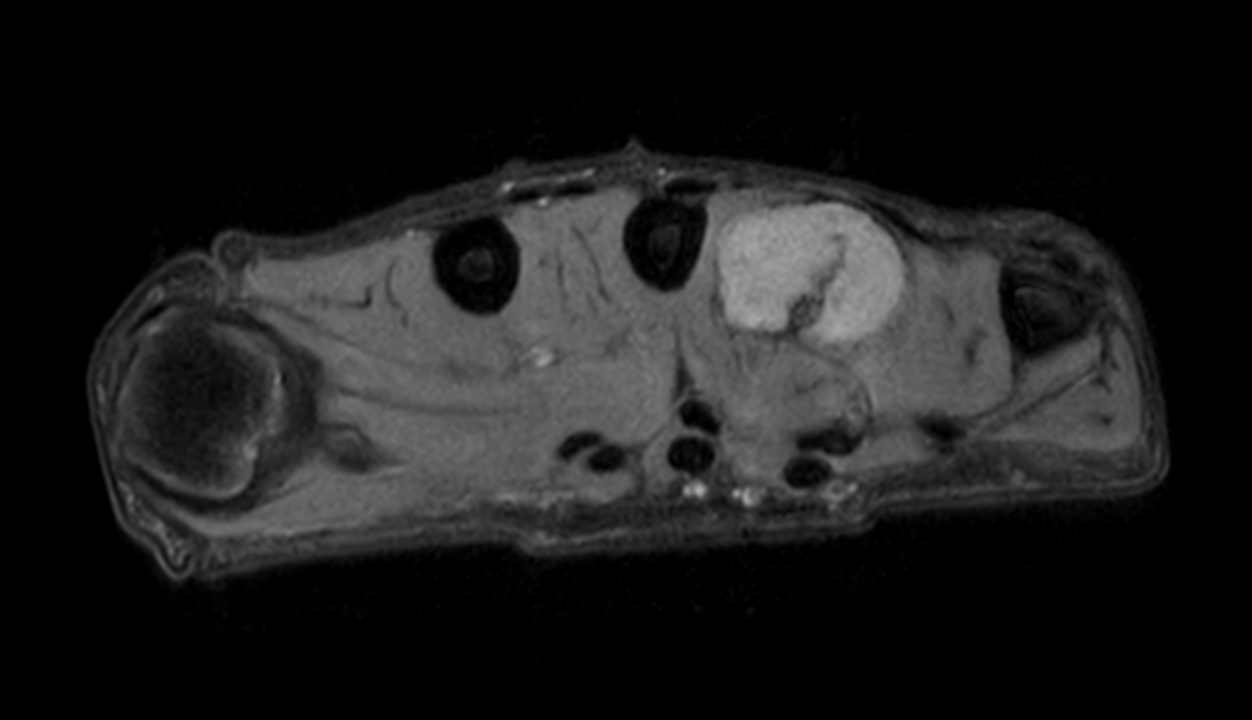

Axial PDw mDIXON XD TSE (Water only)

Axial PDw mDIXON XD TSE (In Phase)

Axial PDw mDIXON XD TSE (Partial FatSat)